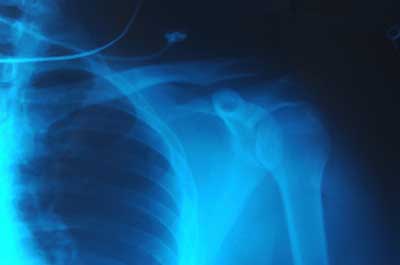

Roentgen placed various objects between the tube and the screen, and the screen still glowed. Finally, he put his hand in front of the tube, and saw the silhouette of his bones projected onto the fluorescent screen. Immediately after discovering X-rays themselves, he had discovered their most beneficial application.

Roentgen's remarkable discovery precipitated one of the most important medical advancements in human history. X-ray technology lets doctors see straight through human tissue to examine broken bones, cavities and swallowed objects with extraordinary ease. Modified X-ray procedures can be used to examine softer tissue, such as the lungs, blood vessels or the intestines.

Generally, doctors keep the film image as a negative. That is, the areas that are exposed to more light appear darker and the areas that are exposed to less light appear lighter. Hard material, such as bone, appears white, and softer material appears black or gray. Doctors can bring different materials into focus by varying the intensity of the X-ray beam.

X-rays are a wonderful addition to the world of medicine; they let doctors peer inside a patient without any surgery at all. It's much easier and safer to look at a broken bone using X-rays than it is to open a patient up.